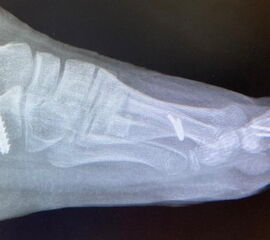

Die Chevron Osteotomie 1 ist ohne Komplikationen am wachsenden Skelett durchführbar. Das Metatarsale I besitzt distal keine Wachstumsfuge, die geschädigt werden könnte. Die „französische Methode nach Marc Elkaim“ eignet sich für Kinder ganz besonders (Abb. 28).

Abb. 28 a-g: Radiologischer Verlauf einer Chevronosteotomie nach dem Verfahren von M. Elkaim mit prä- (a-c drei unterschiedliche Ansichten) und intraoperativen Röntgenbildern in zwei Ansichten (d-e) sowie postoperativ zwei Ansichten (f-g).

Zum Lesen der Bildbeschreibung und zur Vollansicht bitte die Bilder anklicken. Bilder: A. Helmers.

Sie wird über eine eigene Tapetechnik fixiert und kann bei einem erhöhten Intermetatarsale-Winkel alternativ zur Scarf-Osteotomie durchgeführt werden. Nachteile der Methode sind eine deutliche Verkürzung durch die Fräse sowie eine starke Plantarisierung des Metatarsale I Köpfchens. Um die Verkürzung zu vermeiden, wird verlängernd in Richtung des Metatarsale II Köpfchens (nicht wie offen in Richtung Metatarsale IV Köpfchen) osteotomiert. Gleiches gilt für die starke Plantarisierung, die durch den Knochenverlust der Fräse entsteht. Die Korrektur eines kindlichen oder jugendlichen Hallux valgus ist mit der Methode ansonsten suffizient durchführbar. Wird verkürzt, muss ausreichend plantarisiert werden, um eine Transfer-Destabilisierung MT II-IV zu vermeiden.